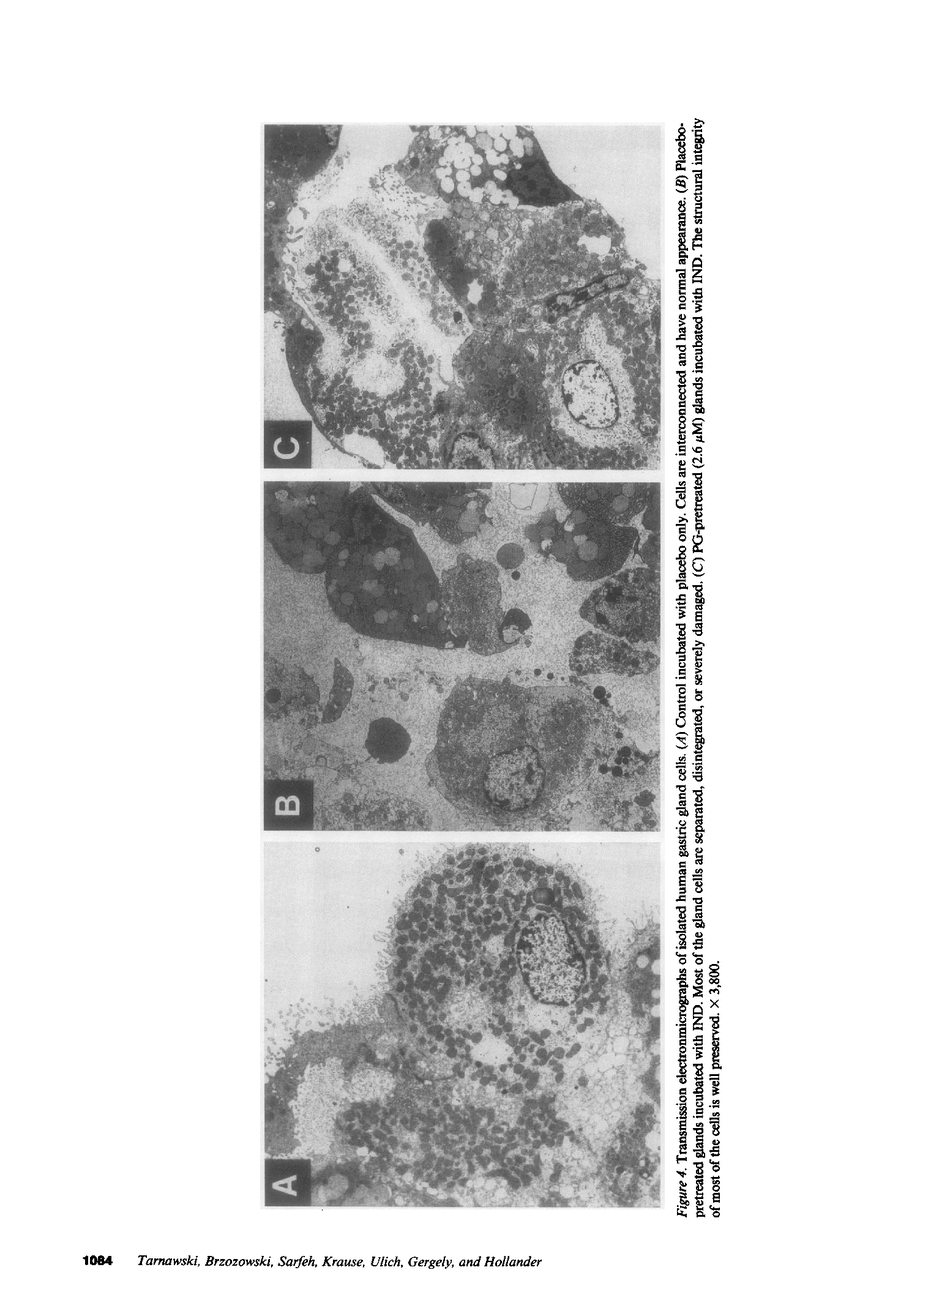

Isolated human gastric glands from surgical specimens were preincubated in an oxygenated medium with placebo or 16,16 dimethyl prostaglandin E2 (dmPGE2) and incubated at 37 degrees C in either medium alone, medium containing 4.43 mM indomethacin or medium containing 8% ethanol. We assessed the viability of gland cells with fast green exclusion, release of lactate dehydrogenase (LDH) into the medium, and ultrastructural damage by scanning and transmission electron microscopy. Both indomethacin and ethanol significantly reduced the viability of placebo-pretreated glands, increased LDH release into the medium, and produced prominent ultrastructural damage. DmPGE2 significantly reduced both indomethacin and ethanol-induced injury, increased the number of viable cells, reduced LDH release, and diminished the extent of ultrastructural damage. These studies indicate that PG protection of gastric mucosal cells has a direct cellular action that is not limited to replacement of depleted endogenous PGs. PG protection in our experiments did not depend on PG's previously described systemic actions, such as protection of the microvessels, preservation of the mucosal blood flow, or stimulation of bicarbonate and mucus secretion.